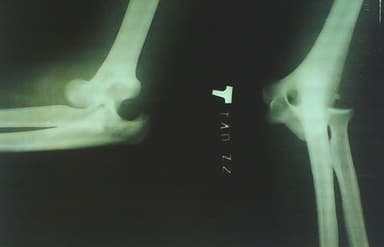

Y tá hoặc bác sĩ có thể kéo vùng khớp bị trật khỏi vị trí ban đầu một cách không quá phức tạp. Tuy nhiên trẻ vẫn có thể bị đau trong và sau quá trình điều trị. Thời gian hồi phục ở trẻ phụ thuộc vào mức độ trật khớp cũng như thời gian bị trật khuỷu tay càng lâu, phục hồi càng chậm. Một số trẻ được chỉ định thuốc giảm đau để giảm thiểu tình trạng này. Nếu khuỷu tay không quay trở về vị trí ban đầu, trẻ sẽ phải chụp X quang để kiểm tra và xác định mức độ tổn thương và áp dụng các phương pháp điều trị phù hợp.